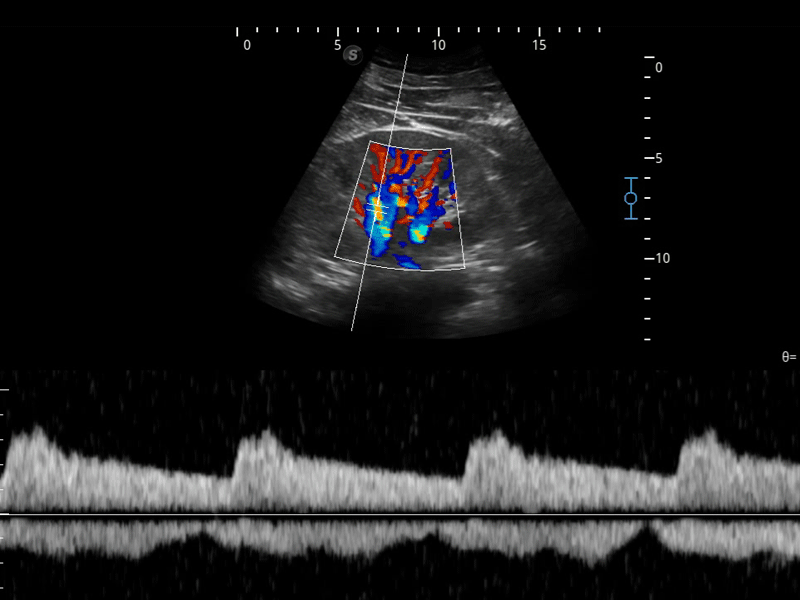

单晶体凸阵探头

凭借狗万官方网站先进的成像技术和优异的探头技术提供的清晰的图像表现,您可以更自信地做出临床决策。